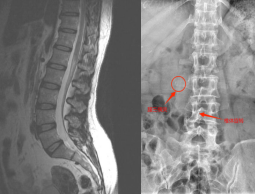

入院后经过进一步的腰椎MRI检查,最终排除了腰椎间盘突出的病因,而困扰患者多年的腰痛很可能是由第三腰椎横突综合征所导致。第三腰椎横突综合征是一种因其特殊解剖位置和特点而引起的无菌性炎症、粘连、变性和增厚,进而刺激腰脊神经,导致腰臀部疼痛的综合征,属于中医“筋伤”“腰痛”的范畴。